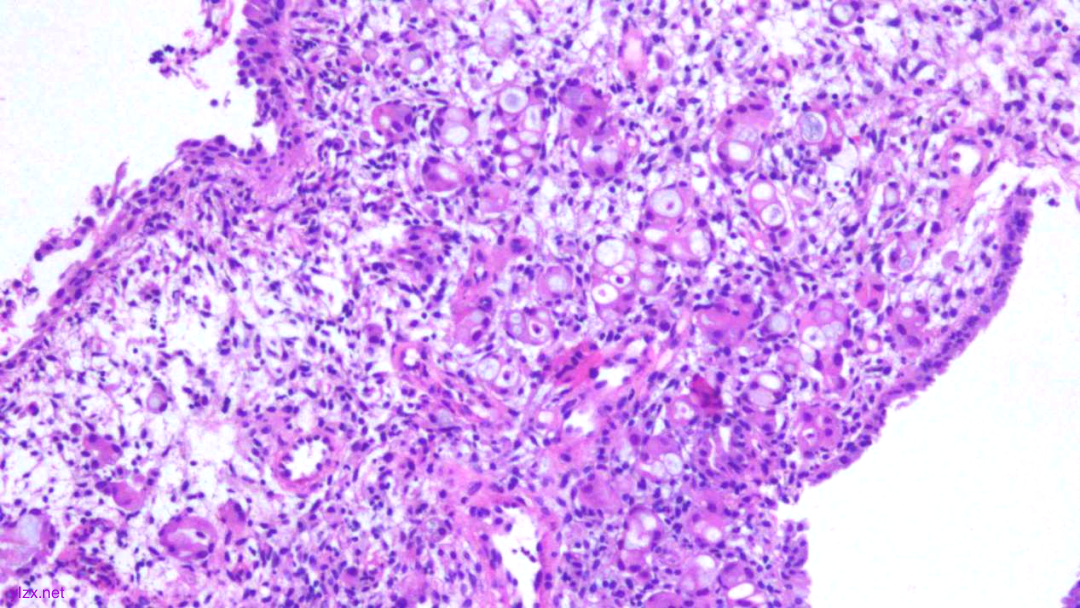

HE:

1.宫颈2点、10点:鳞状上皮下间质内见瘤组织弥漫增生,胞浆宽阔,红染,核小,较一致,部分细胞核偏位,部分细胞可见核仁;

2.宫颈5点:鳞状上皮下间质内见少量异型细胞巢,核增大,深染,浆红染,少量细胞浆内见黏液,印戒样;宫颈管搔刮组织:见血凝块、宫颈内膜组织,间质见异型细胞条索,形态同宫颈5点。

鳞状上皮下间质内见瘤组织弥漫增生,胞浆宽阔、红染,核小,较一致

瘤细胞排列偏稀疏,核小,深染,胞浆红

间质内见异型细胞巢,核增大,深染

间质内见异型细胞条索,核增大,深染,浆红

少量细胞浆内见黏液,印戒样

瘤细胞核偏位,浆红染

高倍瘤细胞见红色核仁